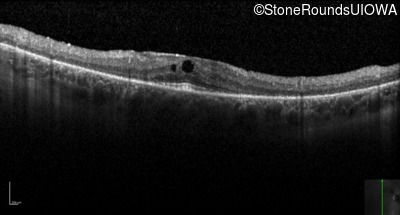

Optical Coherence Tomography - Left - 20/25 -2

Exemplar / OCT Stack